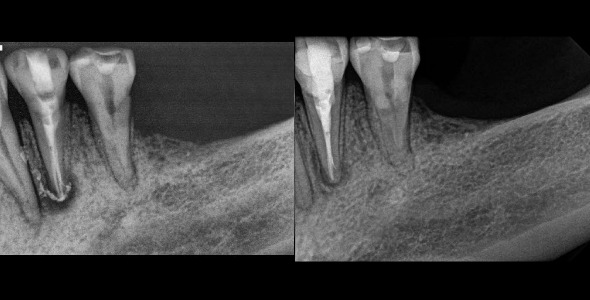

So then this begs the question of how can we obtain straight line access into the canals if we are also trying to avoid these areas and conserve dentin. Straight line access is preached so strongly in most any endodontic course taken and even in continuing education around the world. The answer is that we do not necessarily require straight line access. We can make use of our materials and instruments to access into canals at angles. Specifically nickel-titanium , microscopes, pre-bent handfiles, endodontic explorers, smaller (size 1) mouth mirrors, ultrasonic instrumentation, etc. With a careful and mindful approach to each canal that does not have straight line access we can avoid the complications of file separation, canal transportation or blockage. (figure 9, 10)

Figure 9: A conservative access form very centralized in the tooth. I need to keep this access central so not as to interfere with any lateral walls which would impact the retentive value of the crown to be place. You can see I did not at all have straight line access into the MB or MB2 canals, but the curvature was still managed carefully.

Figure 10: Another very curved canal that I did not attain perfect straight line access on the MB or MB2 canal. The access is very centralized. The illustration on the right with the red shows the location of my access through the crown.